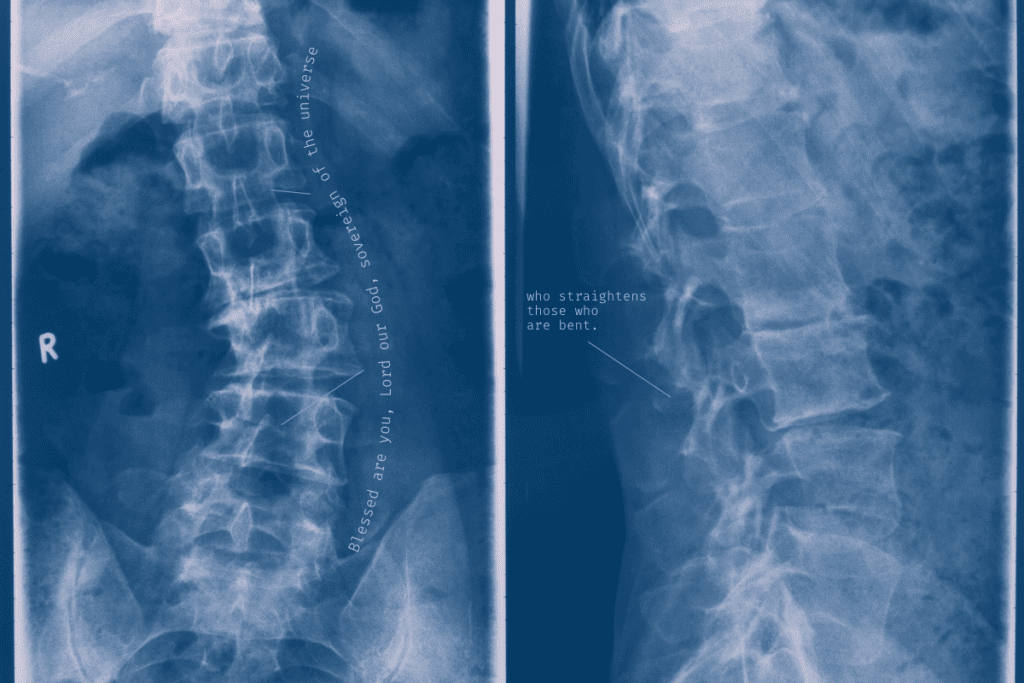

Imaging Studies

Imaging studies are vital to see the spine and find the cause. We use different methods, like:

• X-rays to check vertebrae alignment and look for fractures or wear

• MRI (Magnetic Resonance Imaging) to see soft tissues like discs, nerves, and the spinal cord

• CT (Computed Tomography) scans for detailed bone images